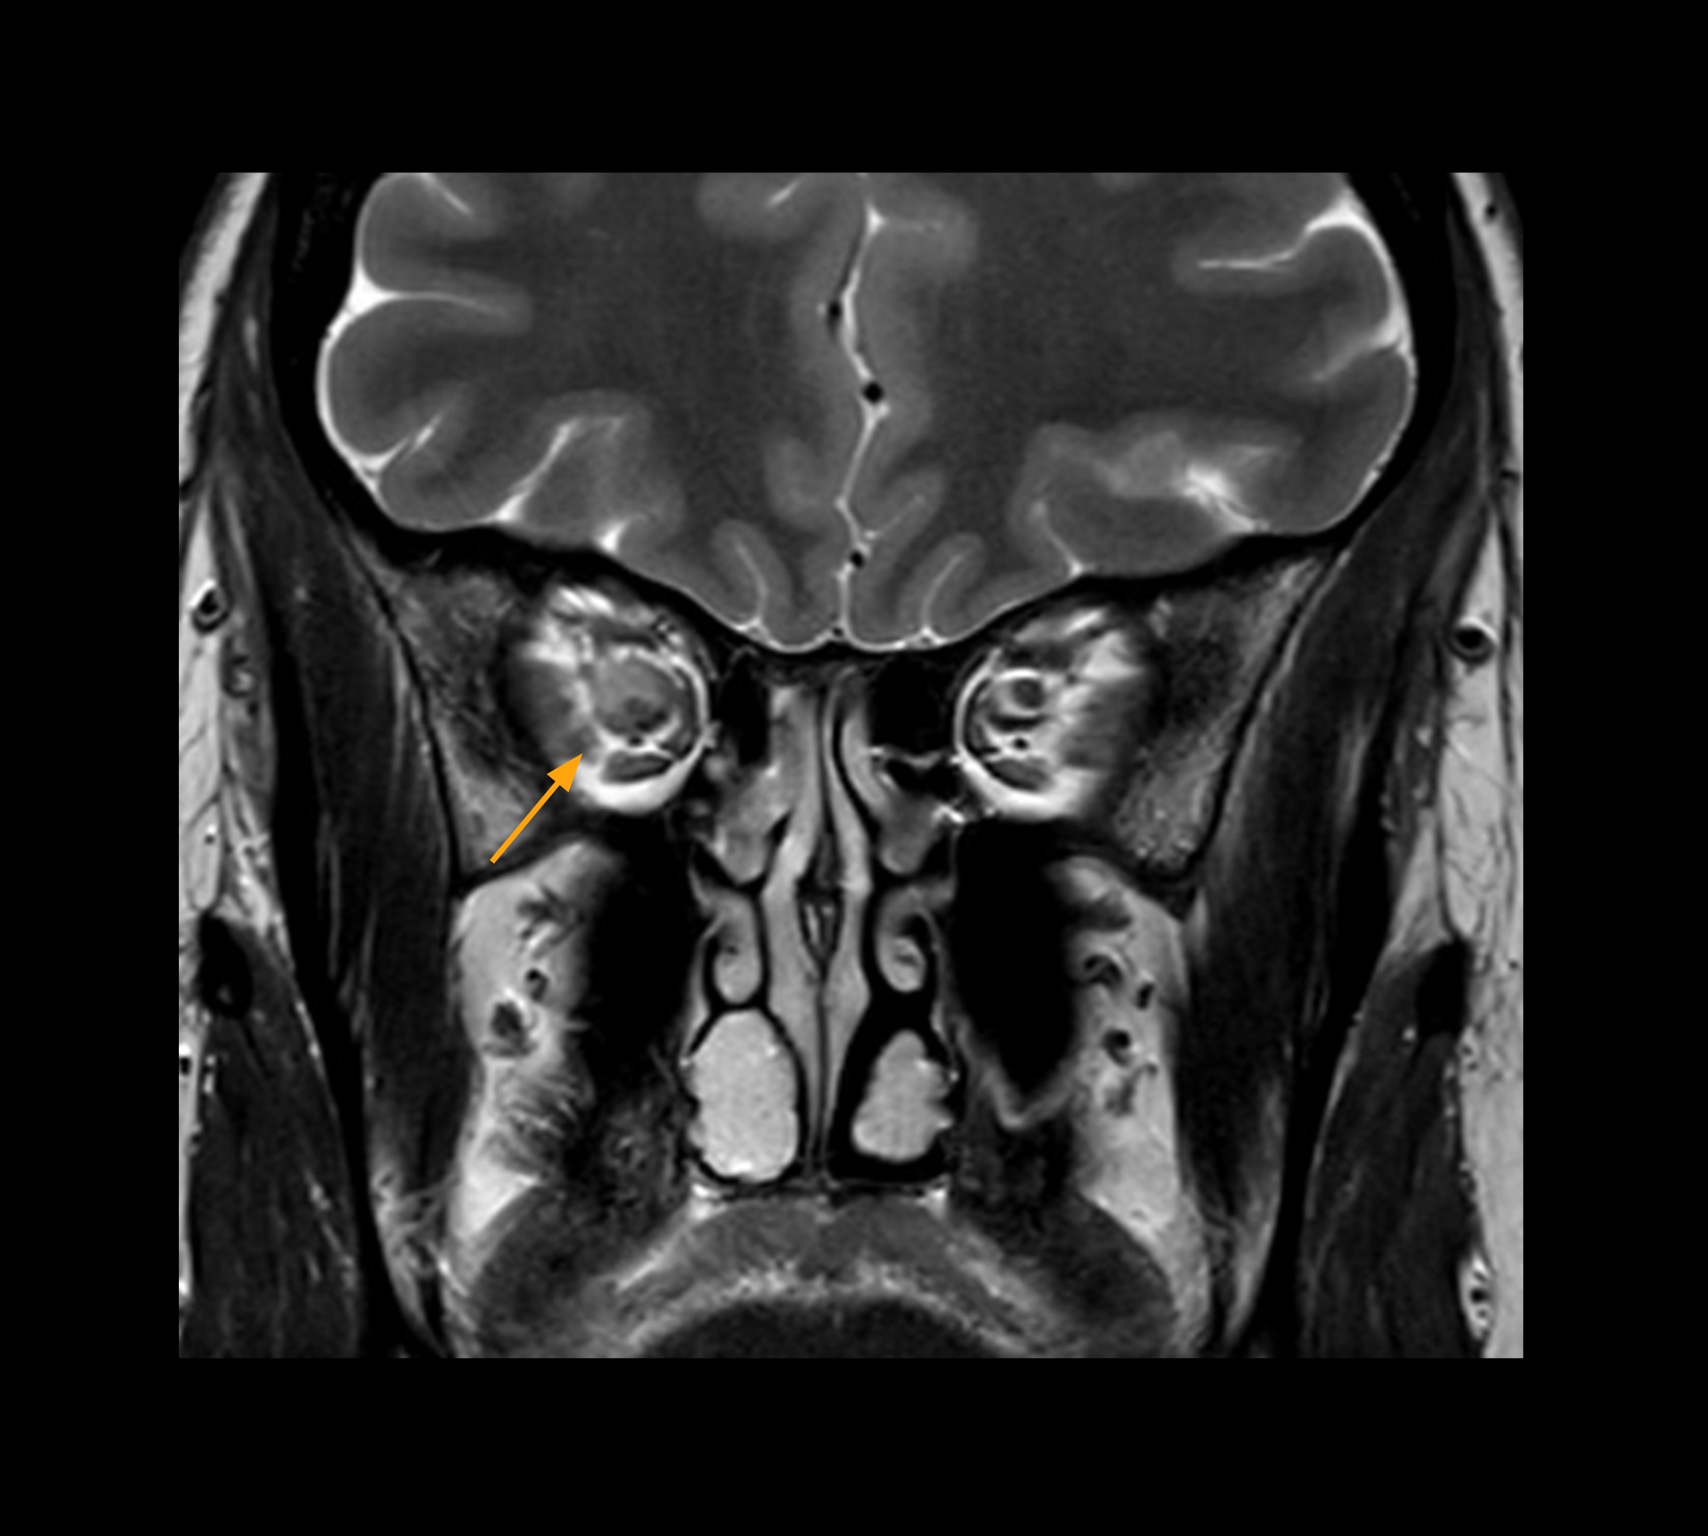

Diffusion weighted imaging of prostate

The examples on the left show the regular clinical diffusion protocol with four b-values up to b1000 s/mm². On the right, the T2W image shows a hypointense lesion that has low ADC and is clearly visible in b1400 and b2000 diffusion images, suggesting malignancy.